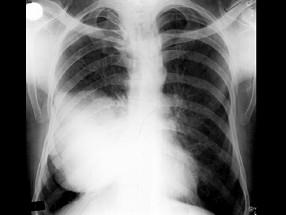

50岁,男性,右侧胸痛、咳嗽、咯血3个月,请结合图像选择最可能的诊断 ( )A、胸膜间皮瘤B、韦格肉芽肿C、肺结核D、肺癌E、纵隔肿瘤

问题 50岁,男性,右侧胸痛、咳嗽、咯血3个月,请结合图像选择最可能的诊断 ( )

选项 A、胸膜间皮瘤 B、韦格肉芽肿 C、肺结核 D、肺癌 E、纵隔肿瘤

答案 D